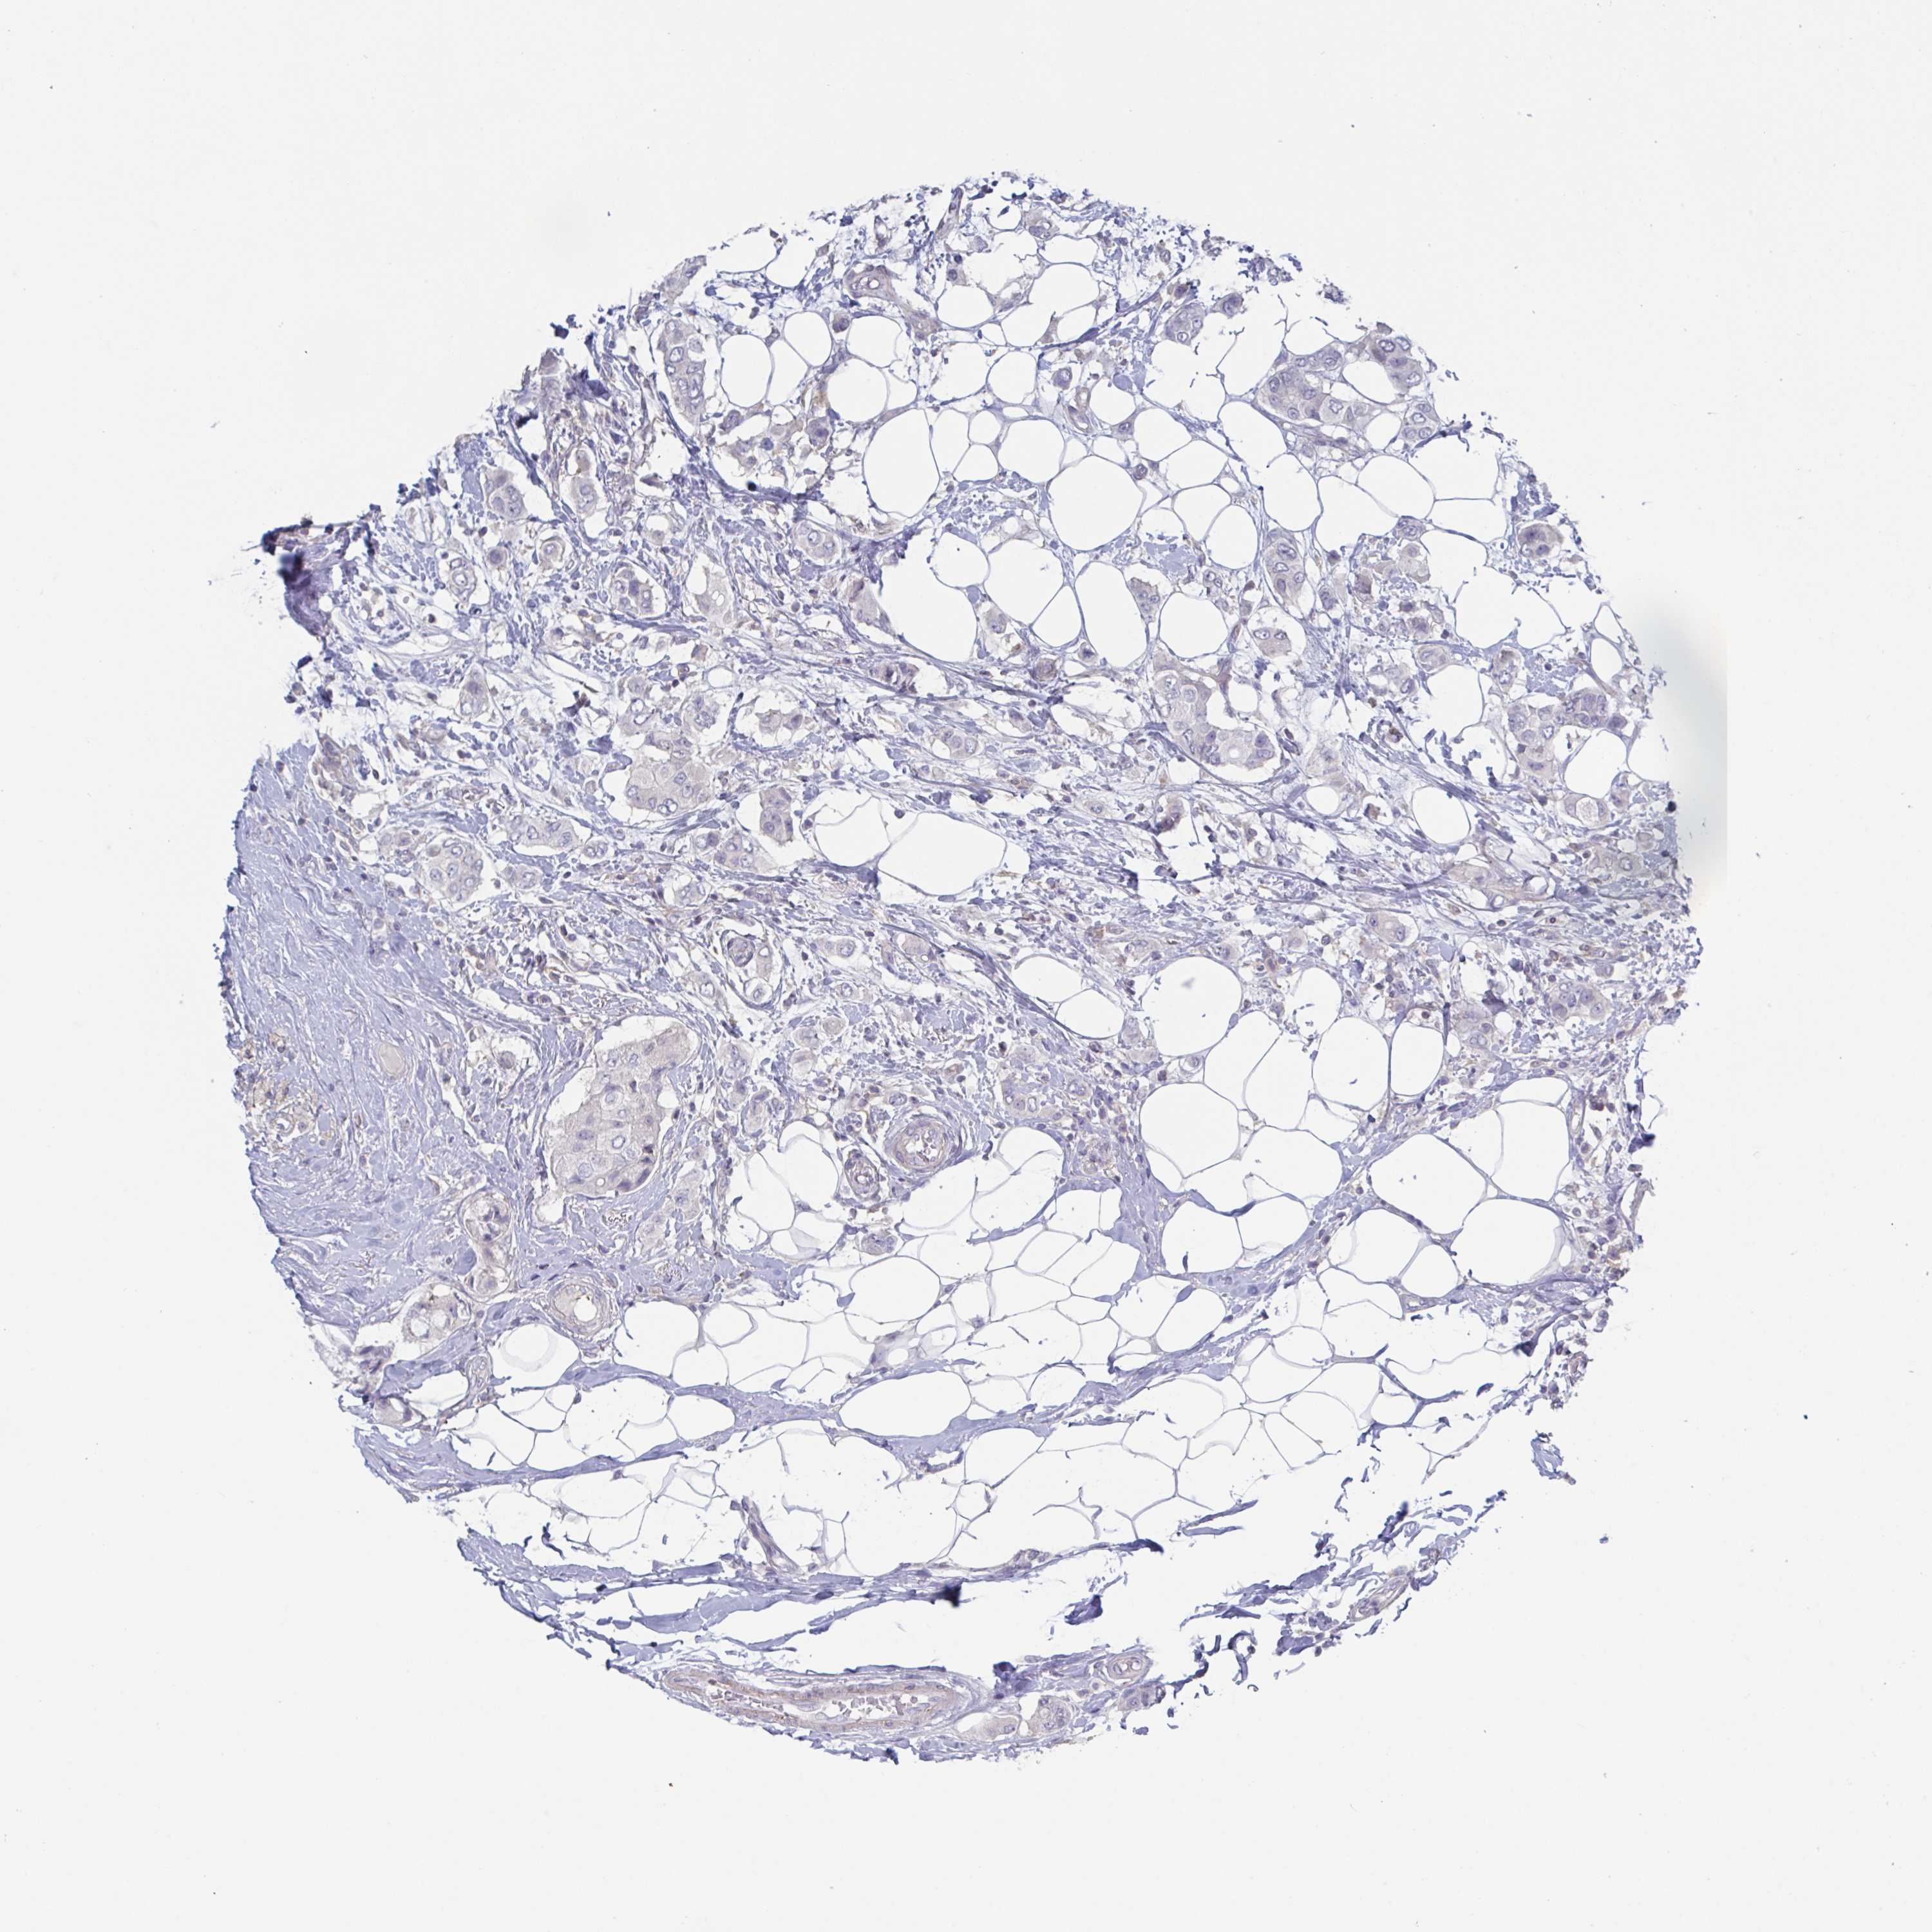

BRCA TCGA BRCA VALIDATION PROTEIN EXPRESSION